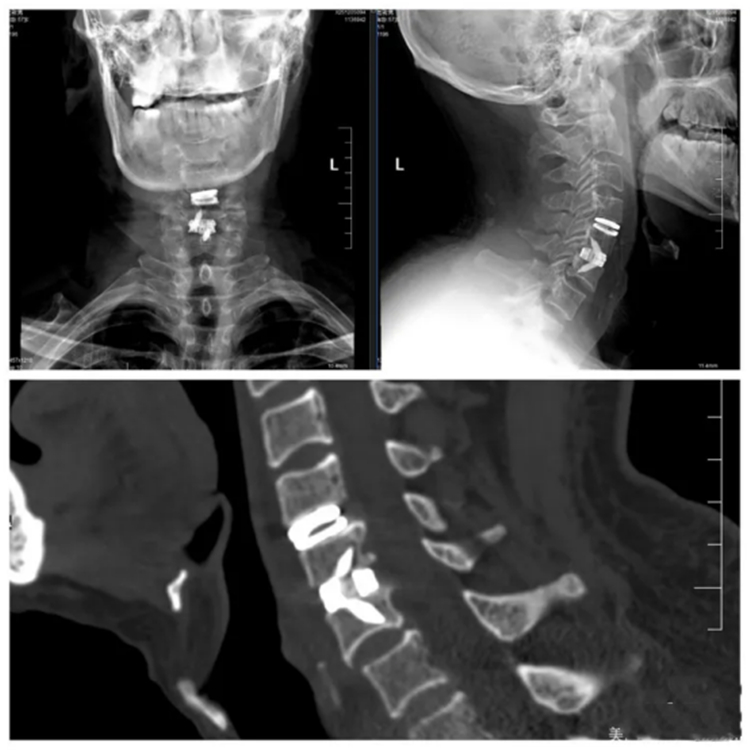

术后影像

该人工椎间盘不仅可维持椎间高度、重建稳定性,更能够保留颈椎前屈、后伸、侧屈及旋转的自然活动功能,从而最大限度维持患者术后颈部的灵活性。手术过程顺利,出血少,神经保护完好。术后第二天,伍大叔即可下地行走,肩颈部疼痛及下肢无力感明显缓解,未出现吞咽不适、声音嘶哑等并发症。复查影像显示,人工椎间盘位置精准,颈椎动态稳定性良好。